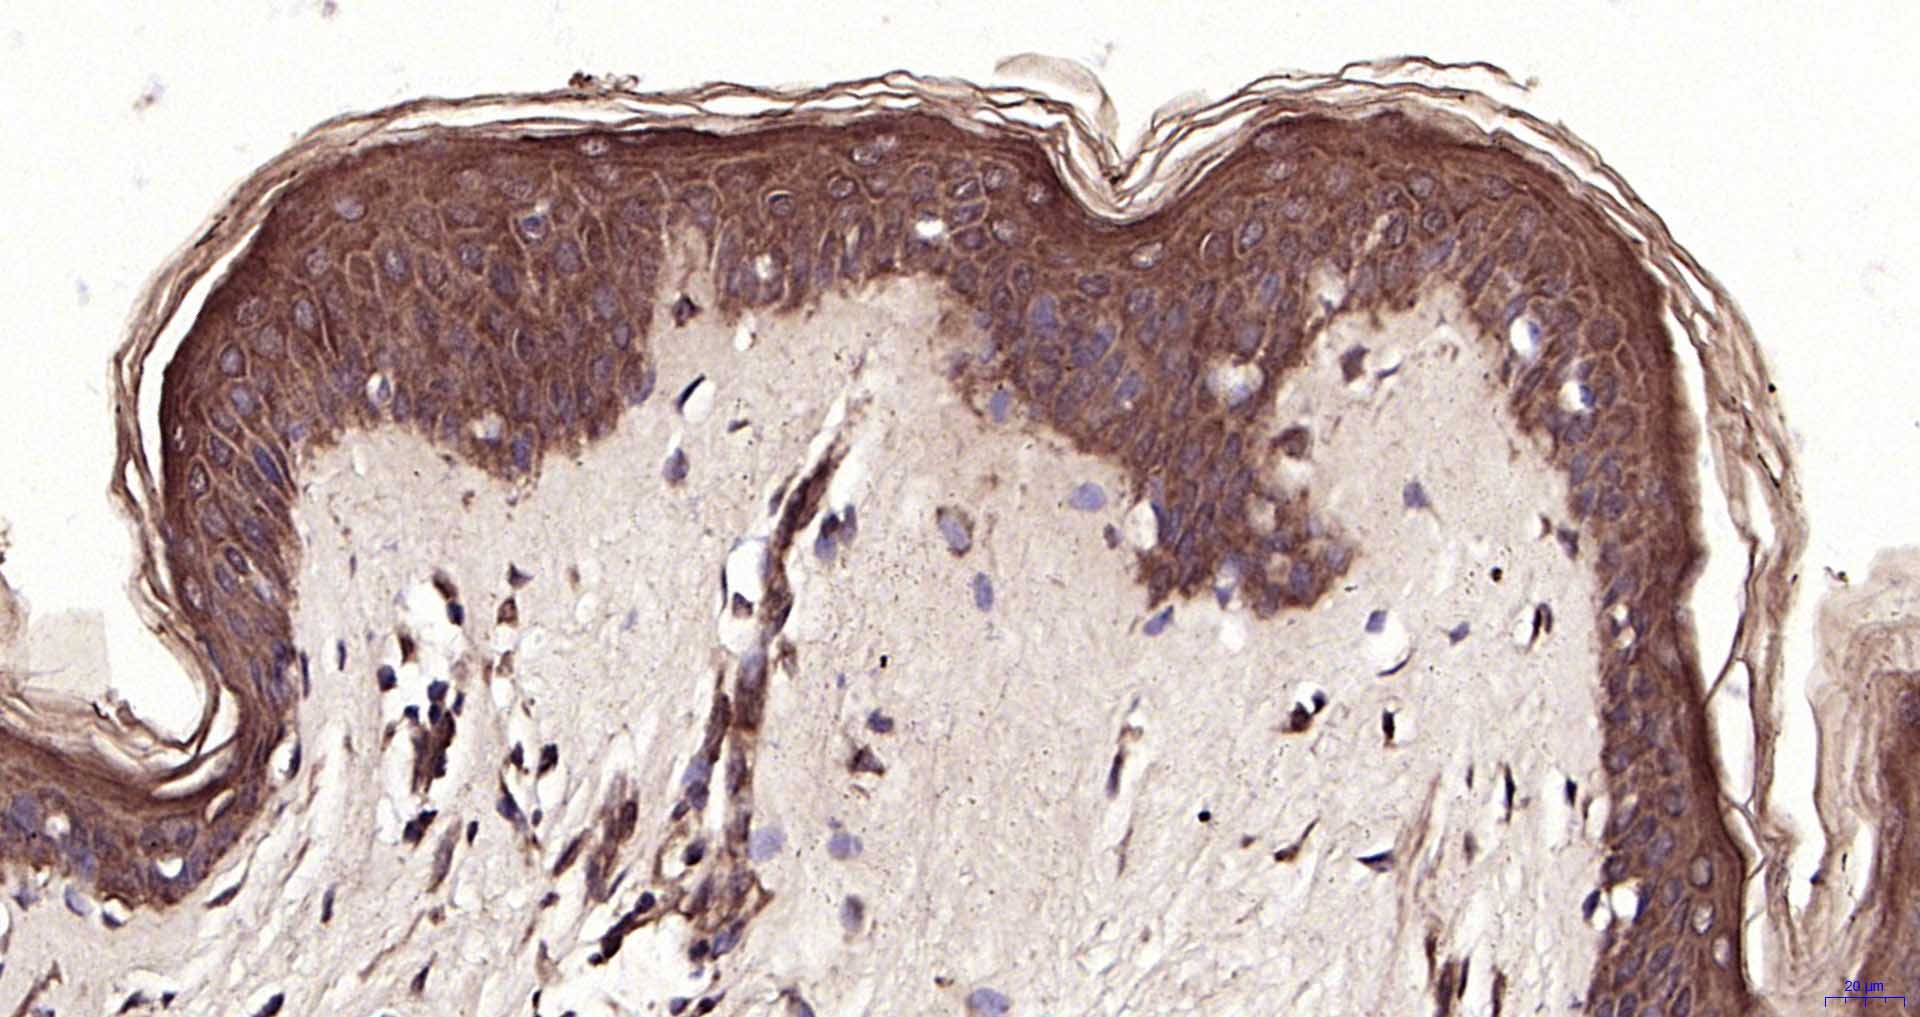

Paraformaldehyde-fixed, paraffin embedded Human Skin ; Antigen retrieval by boiling in sodium citrate buffer (pH6.0) for 15 min; Antibody incubation with PTK6 Polyclonal Antibody, Unconjugated (bs-6266R) at 1:200 overnight at 4°C, followed by conjugation to the SP Kit (Rabbit, SP-0023) and DAB (C-0010) staining.